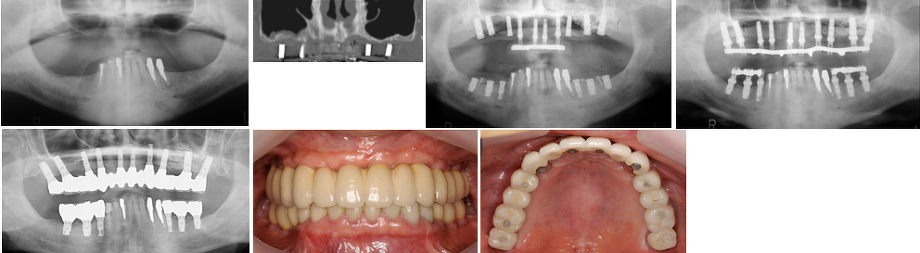

2.サイナスリフト症例(症例 8 )

骨が6mm未満では前述のソケットリフトは長期予後の観点から適応しにくく、骨を確実に増やすにはサイナスリフトの方が適しています。

サイナスリフトとは、上顎洞の側面骨に穴を開け、日ジョイに薄い上顎洞粘膜を剥離し、できた空間に骨補填材を入れ、造骨する手術です。

当院では、サイナスリフトは静脈内鎮静法を併用し局所麻酔で通院で可能です。また、手術時間は片側で約20分で、両側に必要な場合は同時に行い、約40分です。たいていの場合は、インプラントの埋め込みも行いますので、インプラント1本につき約10分ですので、片側サイナスリフトとインプラント2本埋め込みでは約40分で手術は終わります。

サイナスリフトとは、上顎洞の側面骨に穴を開け、日ジョイに薄い上顎洞粘膜を剥離し、できた空間に骨補填材を入れ、造骨する手術です。

当院では、サイナスリフトは静脈内鎮静法を併用し局所麻酔で通院で可能です。また、手術時間は片側で約20分で、両側に必要な場合は同時に行い、約40分です。たいていの場合は、インプラントの埋め込みも行いますので、インプラント1本につき約10分ですので、片側サイナスリフトとインプラント2本埋め込みでは約40分で手術は終わります。